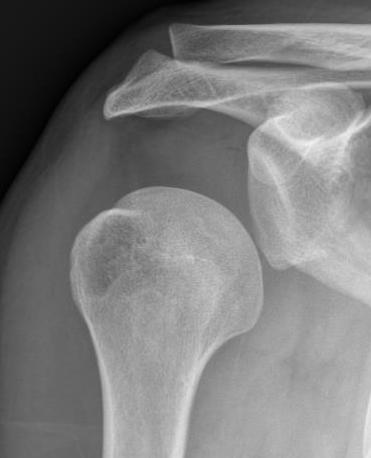

AP Xray

Abnormal overlap of humeral head on glenoid

Light-bulb sign - globular head secondary to internal rotation of the humeral head

Vacant Glenoid Cavity - > 6 mm space between humeral head and anterior rim of glenoid